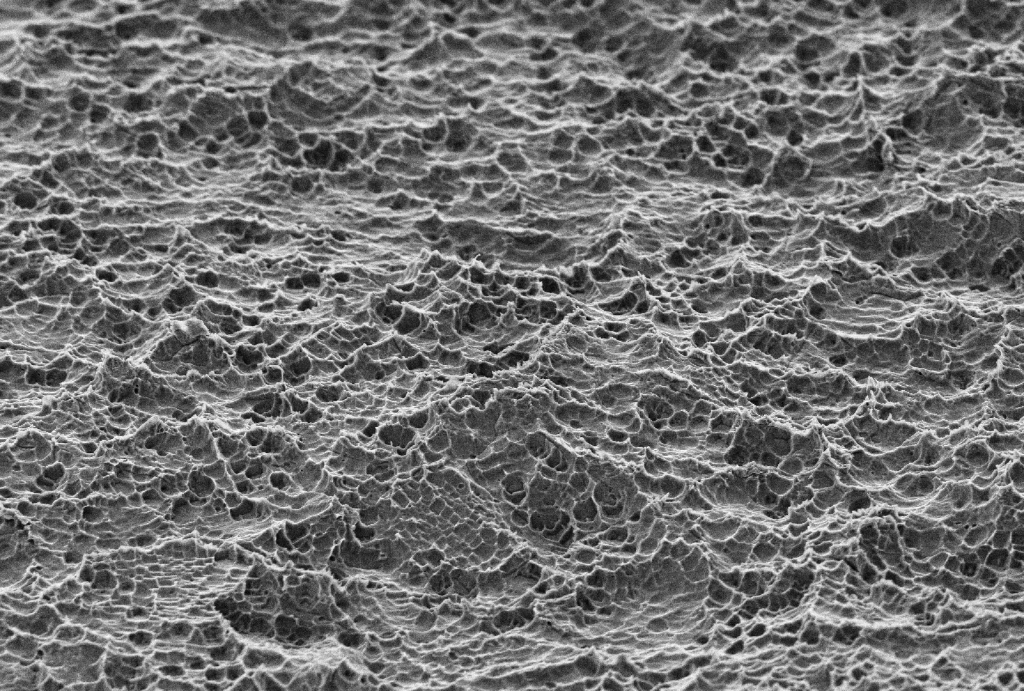

O SUPEX é um tratamento superficial que promove uma área de contato com o osso 100% maior do que os implantes com superfície lisa. Sua superfície rugosa, porém uniforme, é obtida através de um tratamento ácido sequenciado patentead

Esta superfície provê melhores condições de cicatrização e reduz o tempo de osseointegração.

Com esse tratamento conseguimos uma porosidade homogênea [micro e macro porosidade] ideais para a interação entre implante e tecido ósseo.